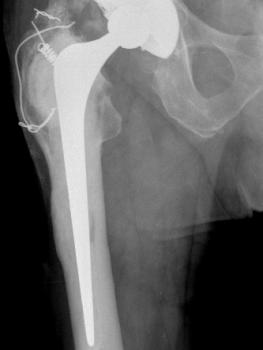

Figure 11 & Figure 12: Cemented fixation in poor bone has the immediate advantage of full weight-bearing in frail patients, especially after trauma.

Figure 13 & Figure 14: In revision hip surgery, the Exeter stem is very versatile for the majority of Paprosky Grade 1 femoral defects. Its length of 15cm conveniently bypasses the 12cm Charnley stem.

Figure 15 & Figure 16: In appropriate cases with a well-fixed cement mantle, the Exeter stem is well-suited to ‘cement-in-cement’ revision technique providing a rapid, atraumatic, bloodless solution for the frail patient.

Figure 17 & Figure18: For larger defects (Paprosky Grade 2) long Exeter stems provide an effective bypass for immediate full weight-bearing with obvious advantages. These are availble in both 37.5 and 44 offset.